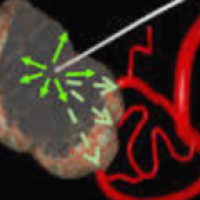

Meningioma

Como a neurorradiologia pode contribuir com o tratamento do meningioma? A embolização...